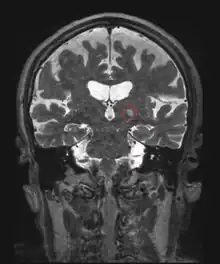

Frontal MRI four days after MRgFUS (MRI-guided high-intensity focused ultrasound): Left ventral intermediate nucleus (Vim) thalamotomy. 79-year-old man with essential tremor.

One of the first applications of HIFU was the treatment of Parkinson's disease in the 1940s. Although ineffective at the time, HIFU has the capacity to lesion pathology. A focused ultrasound system is approved in Israel, Canada, Italy, Korea and Russia to treat essential tremor,[6] neuropathic pain,[7] and Parkinsonian tremor.[8] This approach enables treatment of the brain without an incision or radiation. In 2016, the US Food and Drug Administration (FDA) approved Insightec's Exablate system to treat essential tremor.[9] Treatment for other thalamocortical dysrhythmias and psychiatric conditions are under investigation.[10]